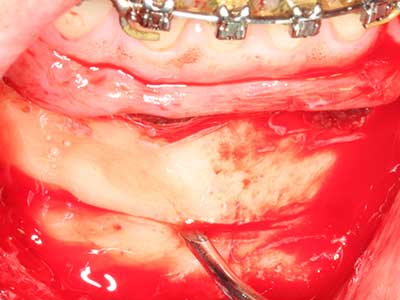

Когато се извършват хирургични процедури върху кост в непосредствена близост до чувствителни структури като кръвоносни съдове или нерви, ротиращите инструменти създават значителен риск за ятрогенно нараняване. Пиезоелектрическите апарати могат да бъдат от помощ при препарация на костно покритие и отстраняване на твърда кост близо до нерви, особено за оголване на нервите след ятрогенно нараняване, както и по време на латерализация на нервите за резекционни и реконструктивни процедури или поставяне на имплант (Фиг. 17-20). Лекият контакт между пиезонакрайника и нерва по принцип не води до нараняване, но ако действате непредпазливо с трионообразни движения или приставки за остатъчен костен субстрат, може да причините временно или перманентно увреждане на нерва. Въпреки това, рискът от увреждане се счита за много по-малък, отколкото при употреба на триони или ротиращи инструменти (Pereira, Gealh et al. 2014).